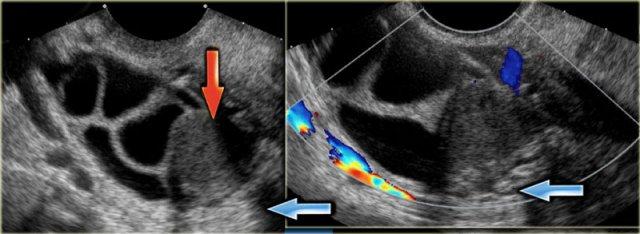

Các hình ảnh siêu âm qua ngã âm đạo cho thấy một nang buồng trứng phức tạp nhỏ với mạch máu thành nang trên phân tích Doppler năng lượng.

Hình ảnh Doppler vòng tròn đặc trưng này được gọi là dấu hiệu ‘vòng lửa’ (ring of fire).

Lưu ý, có hiện tượng xuyên âm tốt và không có mạch máu bên trong, phù hợp với nang hoàng thể đang thoái triển một phần.

Một trường hợp khác với hình ảnh điển hình của dấu hiệu ‘vòng lửa’ trên siêu âm.